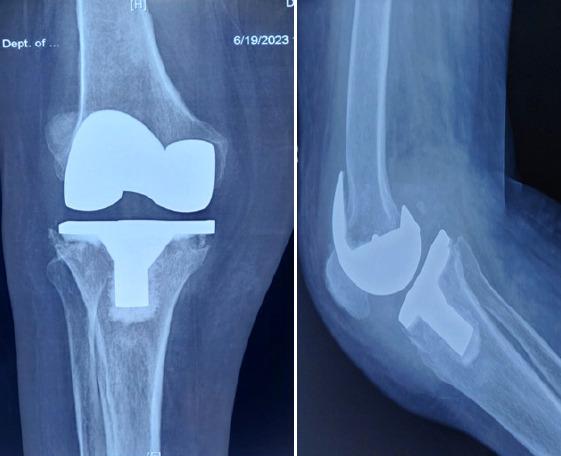

A few cases of periprosthetic infection by A. xylosoxidans have been reported outside India. A periprosthetic infection with A. xylosoxidans following a total knee arthroplasty is reported in a female.

印度以外地区已报道了几例木糖氧化无色杆菌引起的假体周围感染病例。本文报道了一名女性在全膝关节置换术后发生木糖氧化无色杆菌假体周围感染的病例。